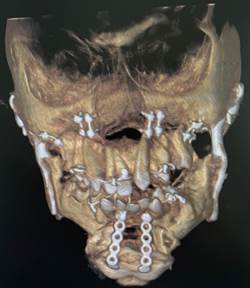

Orthognathic surgery along with the placement of patient-specific implants is usually necessary in such patients. The upper and lower jaws are moved forward along with a counterclockwise rotation of the lower jaw to achieve optimal aesthetic results.

The post-operative CT scan showing the temporomandibular joints on both sides and the titanium miniplates used for fixation of the upper and lower jaw after bijaw orthognathic surgery.